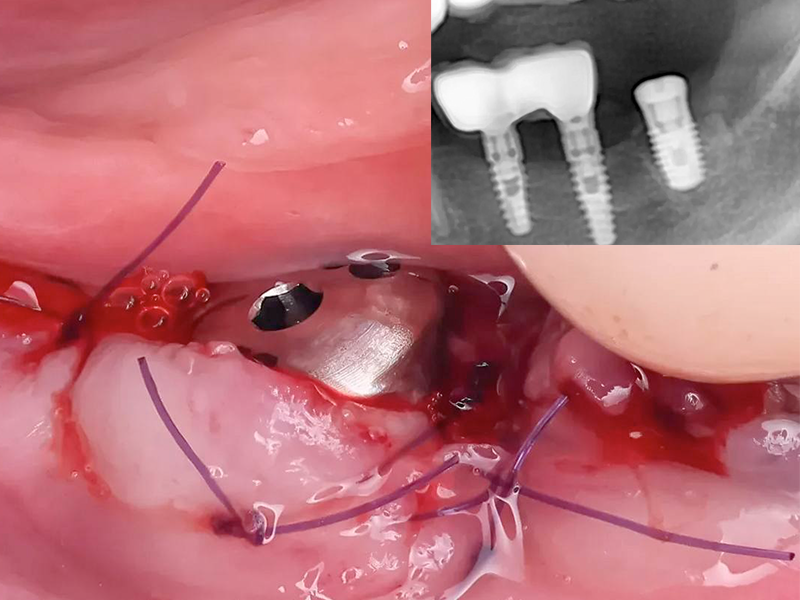

В данном клиническом случае доктором был выбран протокол одномоментной установки имплантата AnyOne Onestage с полированной шейкой и формирователя десны, который идет в комплекте с имплантатом.

Установлен короткий имплант AnyOne Onestage, зафиксирован формирователь десны